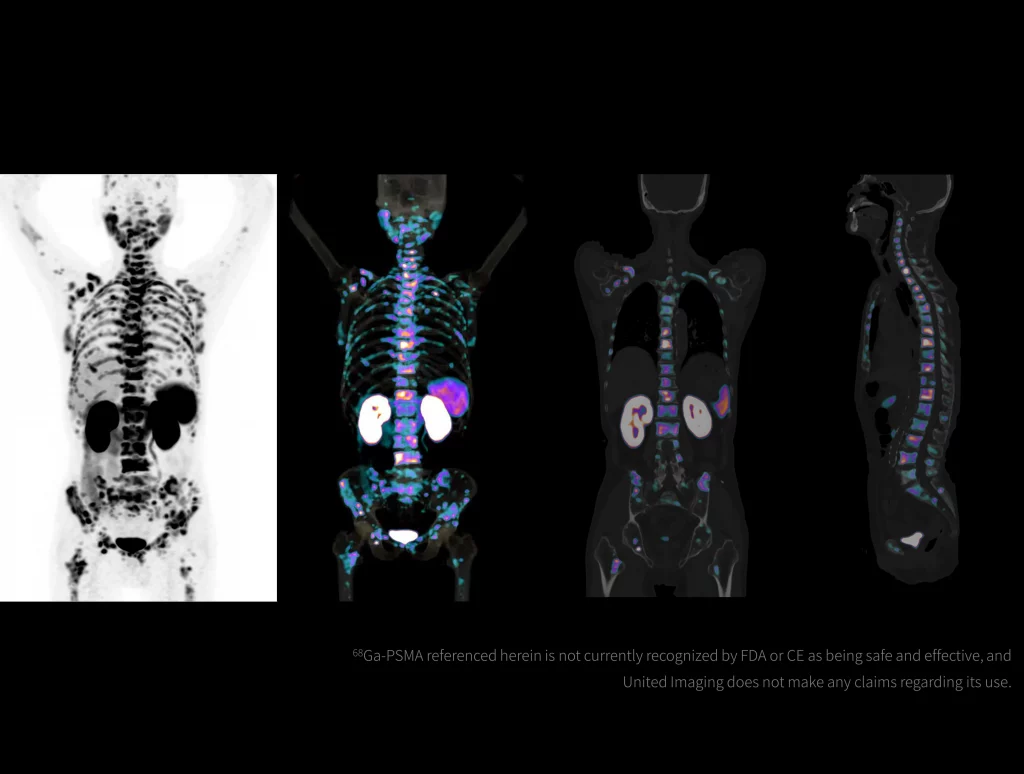

With the ultra-high system performance, uMI Panorama faces up to the challenges of tracers with different half lives and the complex scanning conditions, without compromise for image quality.

New-Tracer Imaging

Click on different tracers to see the images.